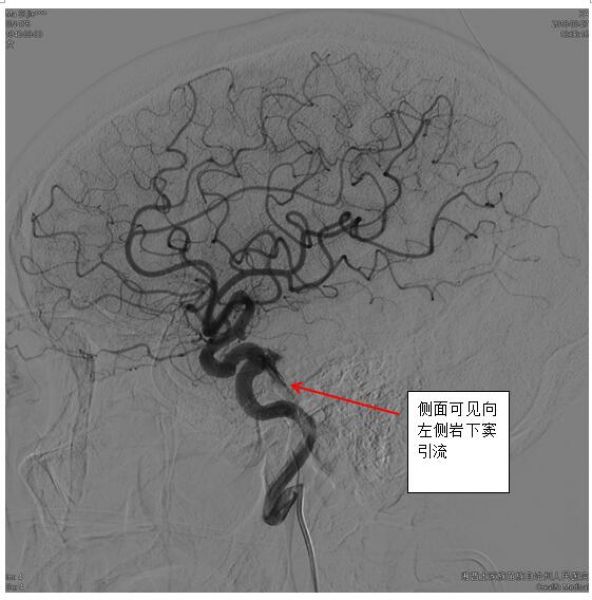

一旦怀疑DAVFs,神经内科一病区医生迅速和患者及家属沟通,及时完成脑血管造影,第一时间确诊患者为海绵窦区DAVFs(供血动脉为左侧颈内动脉海绵窦段,向左侧岩下窦及通过海绵间窦向对侧岩下窦引流)。

最终,经过充分准备,凭借精湛的技术,手术组田勇副主任医师、梁承财主治医师在刘凡教授指导下,在护理人员及麻醉师同力合作下,顺利通过颈内静脉-岩下窦入路,采用弹簧圈辅助加注入onxy胶的方式完全闭塞瘘口,患者术后没有神经功能缺损。